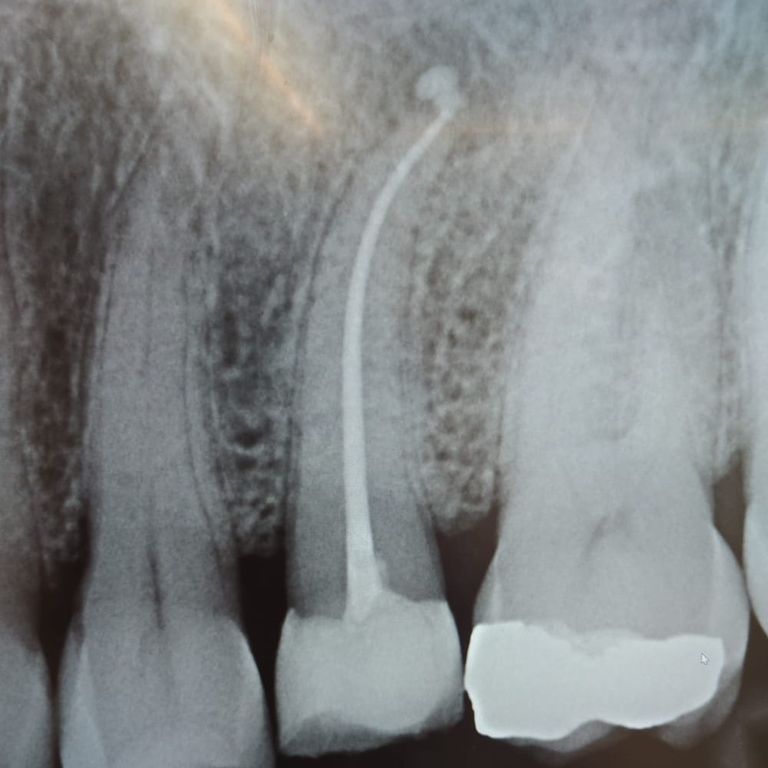

A tooth endodontic treatment is commonly known as a tooth root canal treatment.

With a root canal treatment, the dentist aims to save a tooth by cleaning the tooth including the crown of the tooth and the nerve canals in the roots of the tooth. This is done by cleansing with irrigants and by shaping the canals until they become as free of bacteria as possible.

The root canal treatment is usually needed because the nerve and blood vessels of the tooth have been invaded by bacteria.

These microbes have caused infection and inflammation within the tooth. This process causes the tooth to die and become what your dentist might call: necrotic.

Another cause could be certain inflammation processes and trauma to the tooth.